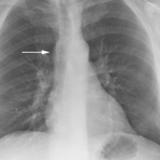

Bronch Cyst 1

arrow